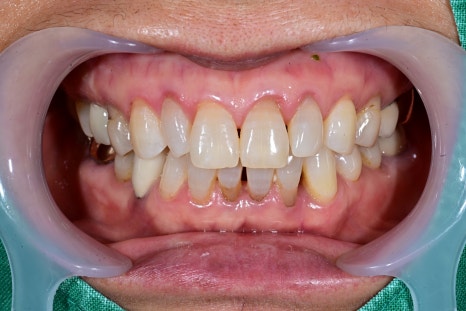

실제로 서울오브치과병원에 내원하신

60대 여성 환자분도 오른쪽 위 어금니가

계속 흔들리는 문제로 방문하셨습니다.

Previous image Next image

검사 결과 잇몸뼈가 많이 약해져 있어

자연치아 유지가 어려운 상태였고,

임플란트를 통해 기능을 회복하기로 결정하게 되었습니다.